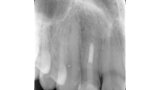

Indikační šíře MTA: Soubor kazuistik